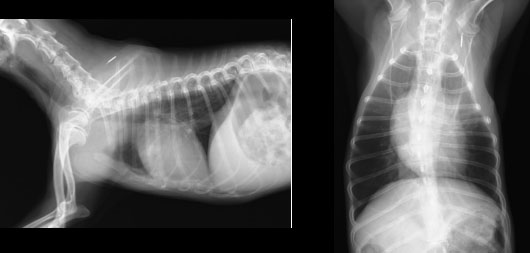

肺の状態を確認するため、胸部レントゲン検査を実施すると、心臓の拡大と肺の不透過性亢進像(白くなること)が確認されました。(図1参照)

図1